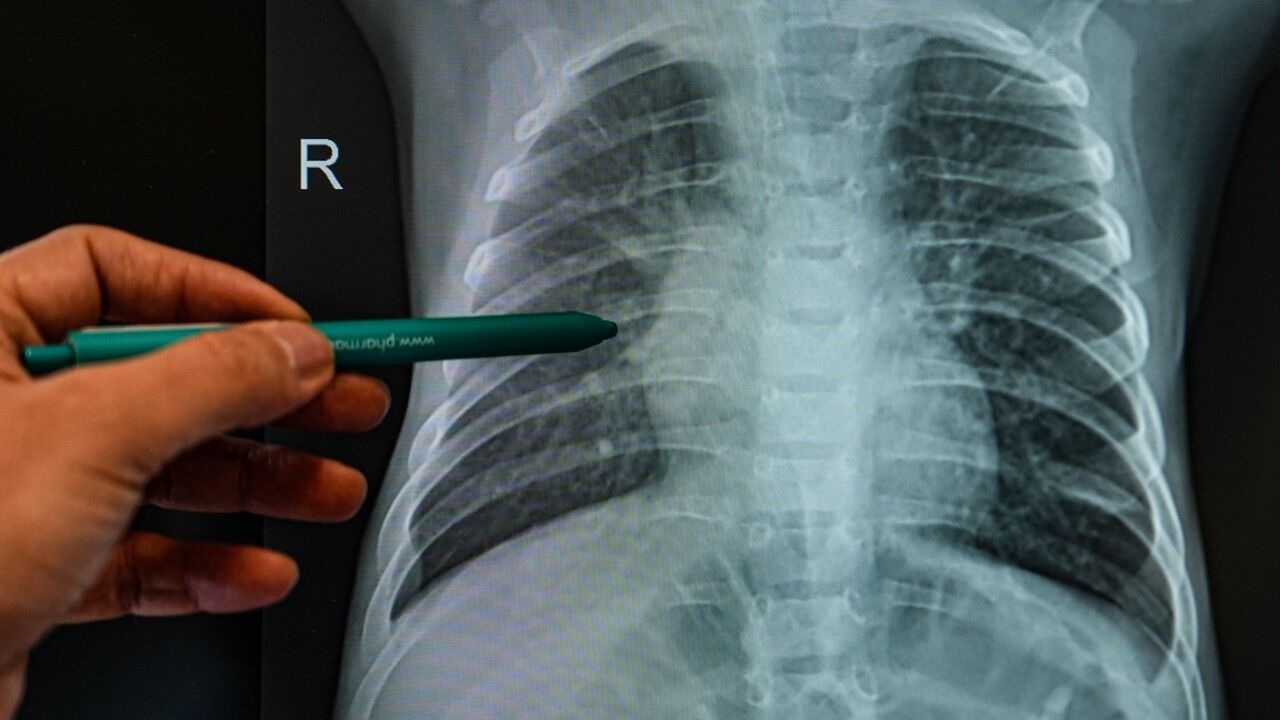

Alerjik çocukların, özellikle astım ve alerjik rinit gibi rahatsızlıkları olanların enfeksiyonlara daha kolay yakalandığını belirten Doç. Dr. Serdar Al, “Alerji ve enfeksiyonlar birbirini tetikleyen durumlardır. Alerjik çocuklarda bağışıklık sistemi belirli proteinler üretir ve bu proteinler enfeksiyon sırasında aşırı salgılanarak alerjik semptomları artırır. Enfeksiyonlar, burun akıntısı, öksürük ve diğer alerjik şikayetleri daha da kötüleştirebilir. Alerjik bireyler, enfeksiyonlara karşı daha hassastır. Bir ortamda virüs taşıyan bir kişi 10 kez hapşırdığında normal bir birey enfekteolabilirken, alerjik bir birey tek bir hapşırıkla hastalanabilir” ifadelerini kullandı.

Özellikle 2 yaş altı çocukların enfeksiyonlardan korunmasının büyük önem taşıdığını vurgulayan Doç. Dr. Serdar Al, “Kış aylarında enfeksiyonlar daha fazla görülüyor. Çocukların okullarda, kreşlerde ve toplu taşıma araçlarında daha fazla zaman geçirmesi bulaş riskini artırıyor. Kapalı ortamlardan mümkün olduğunca uzak durmak, hijyen kurallarına dikkat etmek ve bağışıklık sistemini güçlendirecek önlemler almak önemli. Ayrıca RSV, rinovirüs, influenza, COVID gibi viral enfeksiyonlar (gibi) alerjik hastalıkların gelişimini kolaylaştırabilir” diye konuştu.